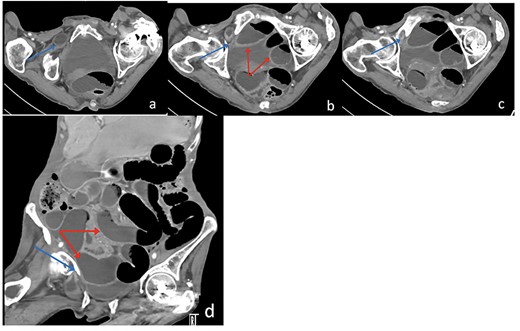

Axial (a–c) and Coronal (d) contrast-enhanced reformatted CT image of the abdomen shows distal ileal loop segment protrudes through the right obturator foramen with the herniated segment trapped between the right obturator externus and pectineus muscles (blue arrow), there is proximal upstream dilated small bowel loops (red arrows). In keeping with high-grade small bowel obstruction due to strangulated obturator hernia.

The patient’s lab results revealed leukocytosis of (12.40 m/mm3), and C-reactive protein of (28 mg/l). Abdominal X-ray demonstrated distended small bowel loops with multiple air fluid levels (Fig. 1). Moreover, CT revealed right sided obturator foramen hernia containing a segment of distal ileum causing high-grade small bowel obstruction, which reached up to 4 cm (Fig. 2). The CT also showed extensive bronchiectasis and consolidation with mucus plugging in the lung base.